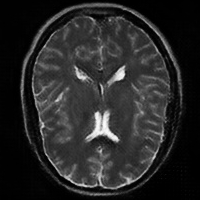

4.4 Qualitative Evaluation

In Figure 5 we analyze the prediction quality of our and compared approaches in a qualitative way. Considering modality propagation in MRI, we see that usage of uncertainty-aware patch invariance (UAPI) gives a better detailed weighting of the cerebrospinal fluid in the middle of the brain. In general, employing patch invariance yields better preservation of fine structures. This observation also applies to accelerated MRI enhancement. In particular, CUT and UAPI provide comparatively sharper knee images with more high-frequency details than the other methods.